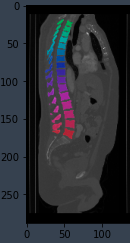

Utility function for superposing a segmentation on top of an image. Image can be single channel or RGB, label is converted to RGB and superposed.

image